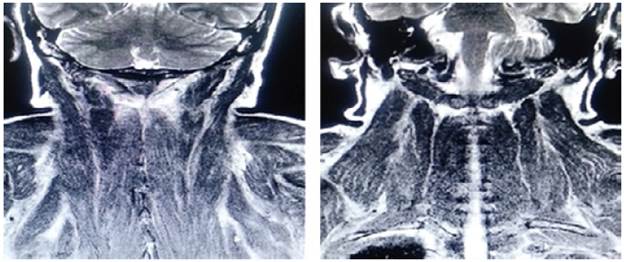

On admission, myopathy studies were initiated (Table 1) and muscle enzymes, electromyography and muscle biopsy were requested, which excluded inflammatory myopathy. The autoimmune profile and HIV were negative. Adult Pompe disease was considered, but acid maltase was normal and syringomyelia was ruled out using contrast-enhanced cervical and brain MRI (Figure 3). Considering the lytic lesions observed in chest tomography, neoplasms (myopathy as a paraneoplastic phenomenon) were looked for as there was no compromise of the pulmonary parenchyma, only bibasal subsegmental atelectasis. No masses or organomegaly were observed in abdomen images (Figure 4).

Contrast-enhanced MRI of the head and neck, coronal plane, with paraspinal muscular edema.

Figure 3: Contrast-enhanced MRI of the head and neck, coronal plane, with paraspinal muscular edema.

Source: Own elaboration based on the data obtained in the study.